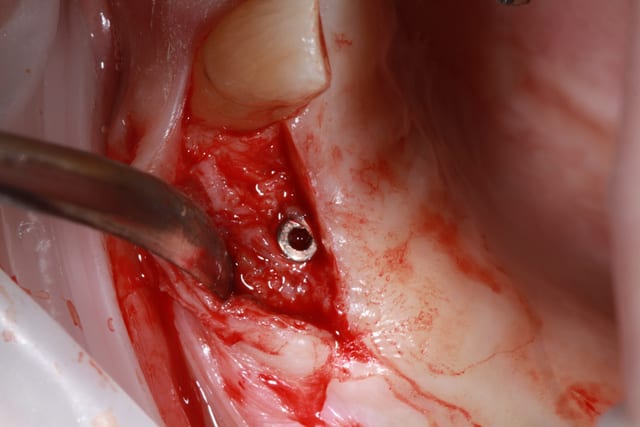

26/03/2014 à 00h13

j'ai posé les vis de cicat. et on va faire la prothèse prochainement.

je ne rajouterai pas d'implant, j'ai du enlever de l'os pour retrouver les vis de fermeture...

les photos